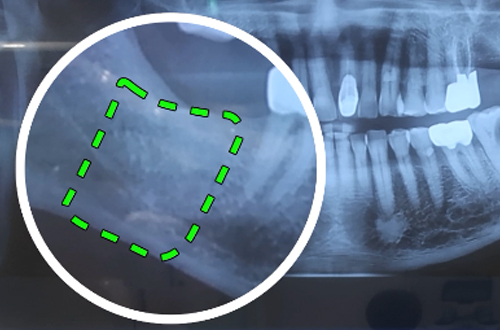

왼쪽 아래 치아를 발치하고 싶어 내원해주셨습니다. 내원 당일 왼쪽 썩은 어금니를 발거하면서 사랑니를 함께 발거 하셨습니다. 이와 동시에 반대쪽 임플란트 식립 상담을 진행하셨는데요. 10년 전 오른쪽 치아를 발거하셨고, 이 빈공간에 임플란트를 식립하기로 계획하였습니다. CT촬영을 판독해본 결과 뼈의 높이와 폭이 충분하다고 판단이 되어 무피판 임플란트 수술을 진행하였습니다. 잇몸의 두께가 충분하여 잇몸 절개 없이 임플란트를 식립해 드렸으며 힐링어버트먼트라고 하는 것을 장착해서 잇몸이 잘 치유가 될 수 있도록 하였습니다. |